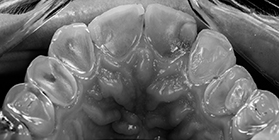

Diagnostic positif et différentiel des formes d’usure

Les conséquences cliniques de l’usure

Thérapeutiques pour les dents faiblement usées